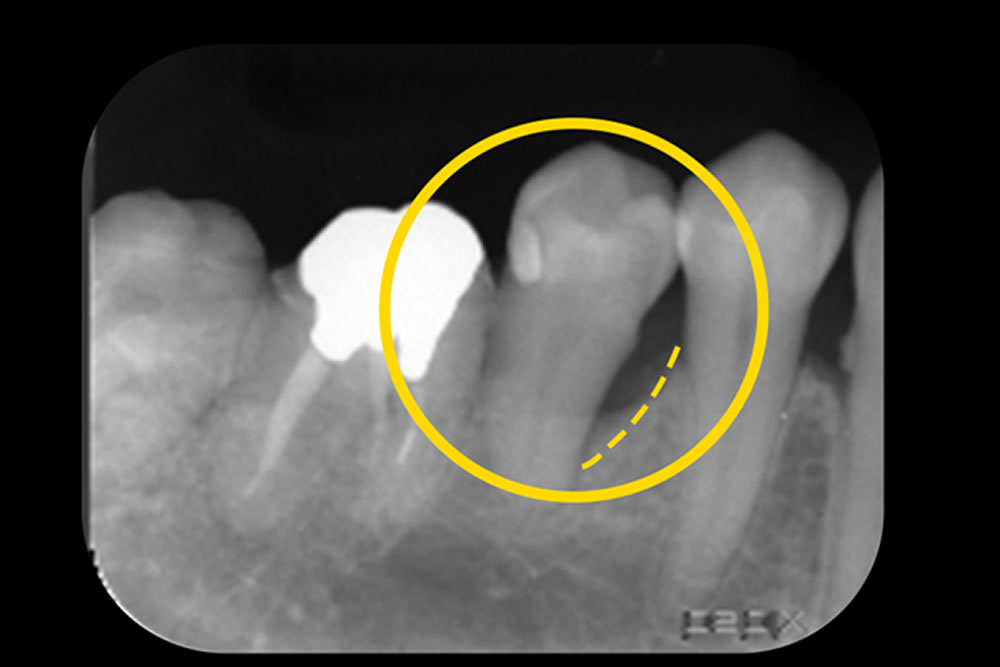

初診時(上写真)、右下6番目の歯は今にも抜け落ちそうな状態でしたが、重度歯周病治療【MINST】によって、症状を改善し、術後1年後(下写真)には歯周組織もしっかりと再生しました。

※外科処置なし・再生材料も使用しておりません。